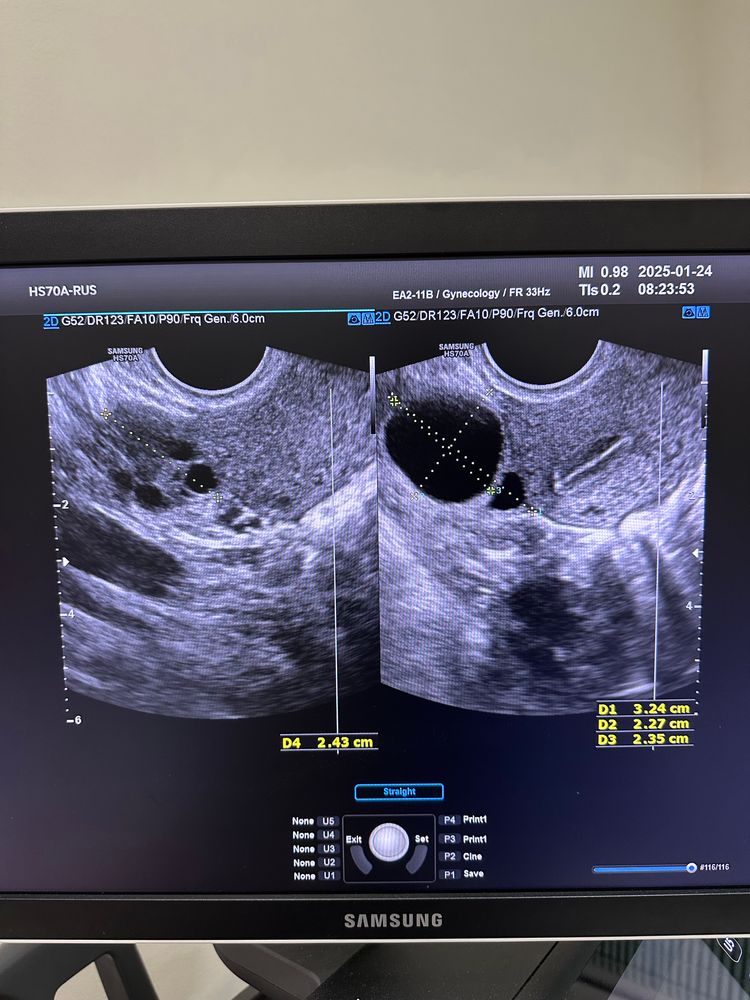

Первая стимуляция. 3 эмбриона без пгт.

Перенос #1 (был заведомо провальный, так как был сделан при налич